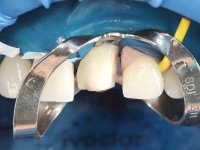

• Confection and bonding of a new feldspathic veneer to replace the fractured one. The new veneer should include a greater distal inter-proximal dental area from tooth 2.1.

• Replace tooth 1.2 veneer with a total crown in feldspathic ceramics, or by a now called 360 veneer.

The axis of insertion of the veneer in relation to the abutment was very carefully evaluated. The feldspathic veneers were prepared in the laboratory and then bonded to the mouth after placing absolute insulation. One year later, we began our third phase of treatment, after the veneer in tooth 2.1 fractured. A dental preparation was done on the bonded veneer, seeking to extend the distal inter-proximal interface more to the palate. The objective would be to move the veneer to a more palatine contact point. Preparation of tooth 1.2 was limited to creating an insertion axis. After preparation, the total crown and laboratory veneer were bonded to the mouth. First, the crown was bonded using a relative insulation with Teflon, later the veneer was bonded after the absolute insulation placement. In the crown, I used this type of insulation to avoid the use of staples. It would be difficult to apply due to the shape and size of the tooth, and would also be aggressive to the soft tissues. After bonding procedures, the occlusal integration of the work was evaluated.